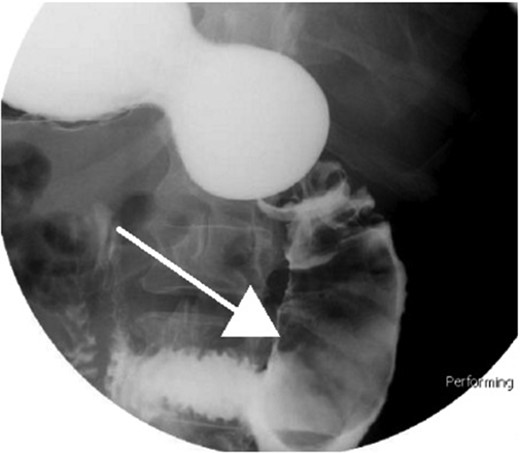

Small bowel series showing duodenal filling defect (posterior view).

With regard to diagnostic workup, the literature has described cases with similar results to ours. Small bowel contrast studies frequently show smooth-walled polypoid filling defects within the duodenal bulb, and CT imaging is useful for delineation of adjacent structures including the common duct and pancreas [1]. Moreover, similar to the pathological results found in our patient, upper endoscopy biopsies are often equivocal as they are submucosal-based lesions [1]. The most useful diagnostic study, however, is endoscopic ultrasound, which may help distinguish the consistency and bowel layer of origin [2, 6], which unfortunately was not available at our institution.